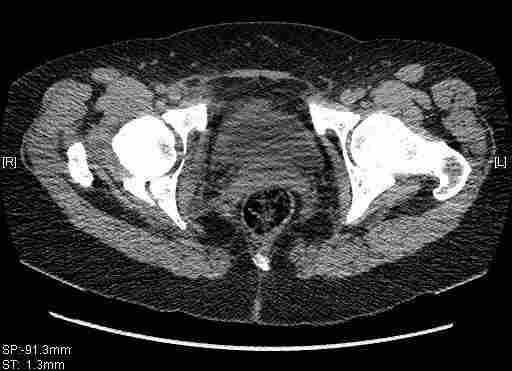

Удалось сегодня вывести пациентку в соседнюю больницу, где есть кт. Срезы сделаны только горизонтальные.